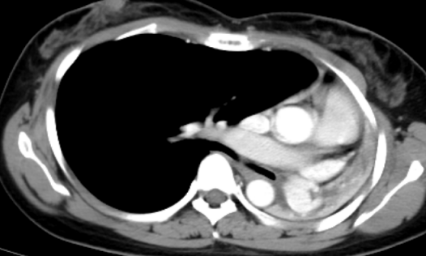

这不看不知道,一看吓一跳!胸部CT结果显示左肺完全不张,病人及家属emo了,“肺没了?”难道从此就要开启“半肺人”的下半生了吗?怎么办?

镜到之处,目之所及:左主支气管开口呈瘢痕样狭窄,远端支气管闭塞。难怪CT上只看到一边的肺,现在真相大白了!患者目前左肺开口处被肺瘢痕完全封堵,形同虚设,只有右肺可以用。